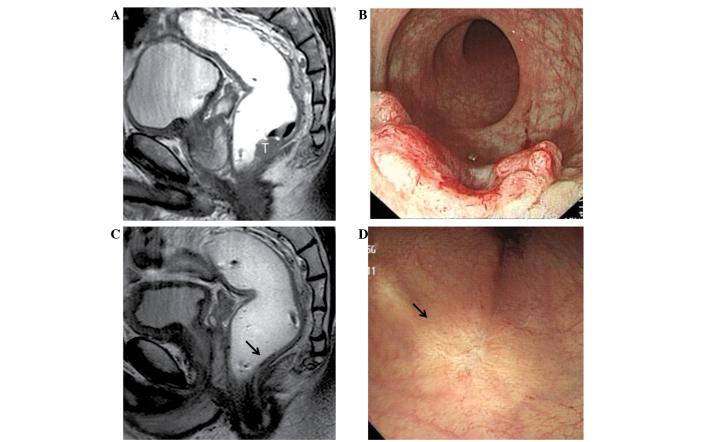

Pre-operative chemoradiotherapy (CRT) for rectal cancer yields a complete tumor response in 10-30% of patients. There is an argument for omitting surgery in these patients, but this remains highly controversial and the supporting evidence based on long-term follow-up is lacking. The present study analyzed the long-term outcomes of five patients with cT3 or cT4 rectal cancer who showed a clinical complete response (ycCR) following pre-operative CRT and underwent no surgery. The ycCR status was determined 7-12 weeks after the completion of CRT using clinical, endoscopic and radiological studies, including magnetic resonance imaging and biopsy. The follow-up period was 54-101 months. Three patients had no tumor recurrence and were alive with no evidence of disease at 101, 100 and 93 months, respectively. One patient developed local recurrence at 59 months and another developed lung metastasis at 32 months. The two patients with tumor recurrence remained disease-free 42 and 22 months after salvage pelvic and thoracic surgery, respectively. Despite being a small series, the long-term survival outcomes of the present study indicate that a non-operative approach may be feasible for a proportion of rectal cancer patients who reveal a ycCR following pre-operative CRT.